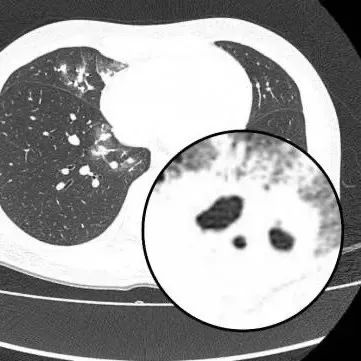

医生查房时,捕捉到CT上形似“鬼脸”的特殊影像(即“鬼脸征”),并伴有“晕伦征”,高度怀疑隐球菌肺炎。医生追问夏女士近期是否曾接触鸟类、禽类及饲养宠物,夏女士否认。

在影像学表现方面,典型CT表现是单发/多发结节伴“晕轮征”,结节液化坏死可形成空洞形似“鬼脸征”,空洞常为薄壁空洞、无液平。